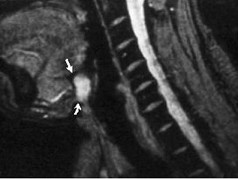

八歲患者,男性,因頸前正中包塊6年入院,查體:頸前正中舌骨下方可觸及一圓形包塊,囊性,無壓痛,隨吞咽上下活動。

8.患者腫塊圖像及影像學檢查結果見下圖,本患者應考慮為  (    )

9.如果考慮為你所選的上述疾病,手術前應該完善下面那個檢查  (    )

正確答案:8.A;9.A